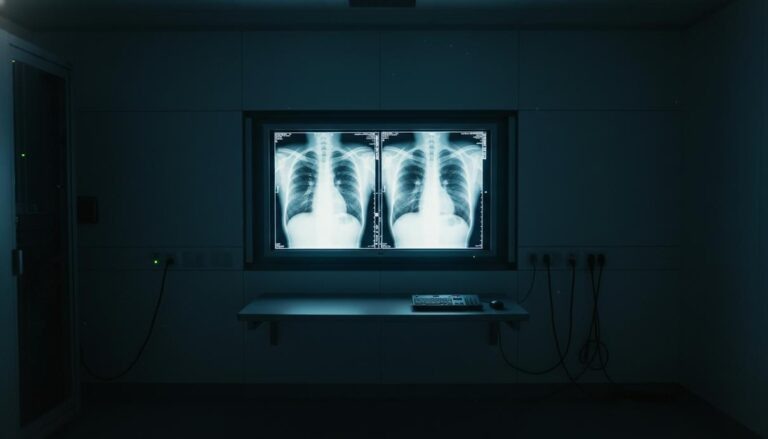

Исследование, опубликованное в журнале Radiology, показало, что опытные рентгенологи и современные мультимодальные языковые модели испытывают серьезные трудности с идентификацией медицинских изображений, созданных при помощи искусственного интеллекта. Специалисты не всегда могут отличить подлинные рентгенограммы от глубоких фейков, что ставит под угрозу безопасность цифровых архивов и достоверность диагностики.

В эксперименте приняли участие 17 врачей из 12 медицинских учреждений США, Франции, Германии, Турции, Великобритании и Объединенных Арабских Эмиратов. Профессиональный стаж участников варьировался от начинающих резидентов до экспертов с сорокалетним опытом. Специалисты из Школы медицины Айкана на горе Синай в Нью-Йорке подготовили для теста 264 снимка, половина из которых была синтезирована нейросетями.

Результаты проверки продемонстрировали, что бдительность врачей напрямую зависит от их информированности о возможных манипуляциях. Если рентгенологам не сообщали о наличии подделок в массиве данных, они успешно распознавали фальшивые снимки лишь в 41% случаев. После предупреждения о присутствии синтетического контента средняя точность идентификации выросла до 75%. При этом личные показатели медиков существенно разнились: точность определения изображений, созданных ChatGPT, колебалась в диапазоне от 58% до 92%.

Сами алгоритмы также оказались несовершенны в вопросах верификации контента. Модели GPT–4o, GPT–5, Gemini 2.5 Pro и Llama 4 Maverick показали точность от 57% до 85%. Примечательно, что даже GPT–4o, использованная для генерации части снимков, не смогла выявить все собственные имитации, хотя и справилась лучше конкурентов. При оценке рентгенограмм грудной клетки, созданных моделью RoentGen от Стэнфордского университета, точность искусственного интеллекта составила от 52% до 89%, в то время как показатели врачей находились в пределах 62–78%.

Авторы работы подчеркивают, что многолетний стаж не гарантирует успеха в поиске подделок – некоторое преимущество имели лишь узкие специалисты в области скелетно-мышечной радиологии. Основными признаками фальсификации оказались избыточная четкость и симметрия. На синтетических снимках кости выглядят слишком гладкими, позвоночник – неестественно прямым, а легочный рисунок и сосудистая сетка – чрезмерно однородными. Переломы на таких изображениях часто выглядят слишком «чистыми» и локализованными на одной стороне кости.